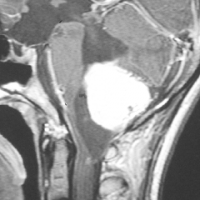

フォン・ヒッペル・リンドウ病の患者さんの脊髄(胸髄)にできた血管芽腫です。上下の脊髄が腫れたり,脊髄の中に空洞(腫瘍のう胞あるいは脊髄空洞症といいます)ができます。 手術治療は症状が出るまで,あるいは症状がかなり強くなってからしかしません。なぜなら,たくさんできる(多発)することが多くて,複数回の手術になってしまうこともあるからです。手術をするたびに,四肢のしびれや麻痺などの後遺症がのこる可能性もあるので,この手術は,脊髄腫瘍の手術経験が相当にたくさんある脳外科医にしかできません。